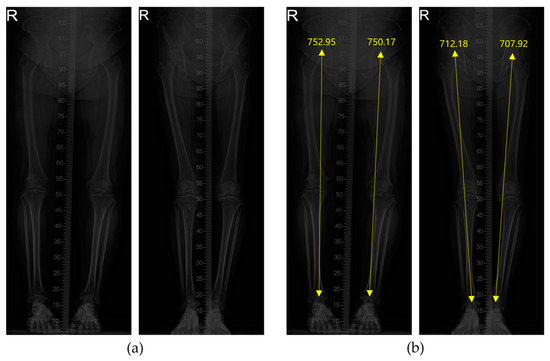

2.3.3. Calculating the Euclidian Length Between Two Key Points

| Test Data Number | Ground Truth (mm) | Measured Length (mm) | Deviation (mm) | |||

|---|---|---|---|---|---|---|

| Left | Right | Left | Right | Left | Right | |

| 1 | 793.2 | 787.2 | 792.94 | 787.43 | 0.26 | 0.23 |

| 2 | 828.6 | 827.5 | 830.56 | 826.74 | 1.96 | 0.76 |

| 3 | 790.6 | 784.5 | 790.09 | 783.66 | 0.51 | 0.84 |

| 4 | 889.6 | 886.0 | 892.12 | 883.52 | 2.52 | 2.48 |

| 5 | 815.9 | 817.2 | 817.05 | 816.43 | 1.15 | 0.77 |

| 6 | 852.4 | 860.2 | 849.73 | 858.08 | 2.67 | 2.12 |

| 7 | 743.9 | 725.9 | 743.59 | 724.90 | 0.31 | 1.00 |

| 8 | 756.9 | 781.7 | 755.65 | 783.79 | 1.25 | 2.09 |

| 9 | 766.9 | 763.6 | 766.93 | 766.54 | 0.03 | 2.94 |

| 10 | 691.5 | 694.7 | 693.27 | 694.83 | 1.77 | 0.13 |

| Mean | - | - | - | - | 1.57 | 1.45 |